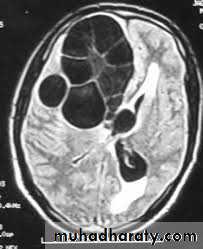

Meningioma

Benign tumor arise from the arachnid cells of the meningeal covering of the brain are most common primary intracranial neoplasm

Usually present in middle age female

it is well defined extra axial , located mainly at the convexity of the skull periphery

CT finding

meningioma presented as isodense area or slightly hyper density area with surrounded crescent of hypo density ( csf cap ) post contrast injection the lesion enhance homogeneously with enhancing Dural tail .

20 % show calcification

hyperostosis & thickening of the near by bony part of the skull & diplioc space .

it may be associated with little or no peri focal edema .

if the lesion associated with central necrosis with large perifocal edema meningio sarcoma should be excluded .